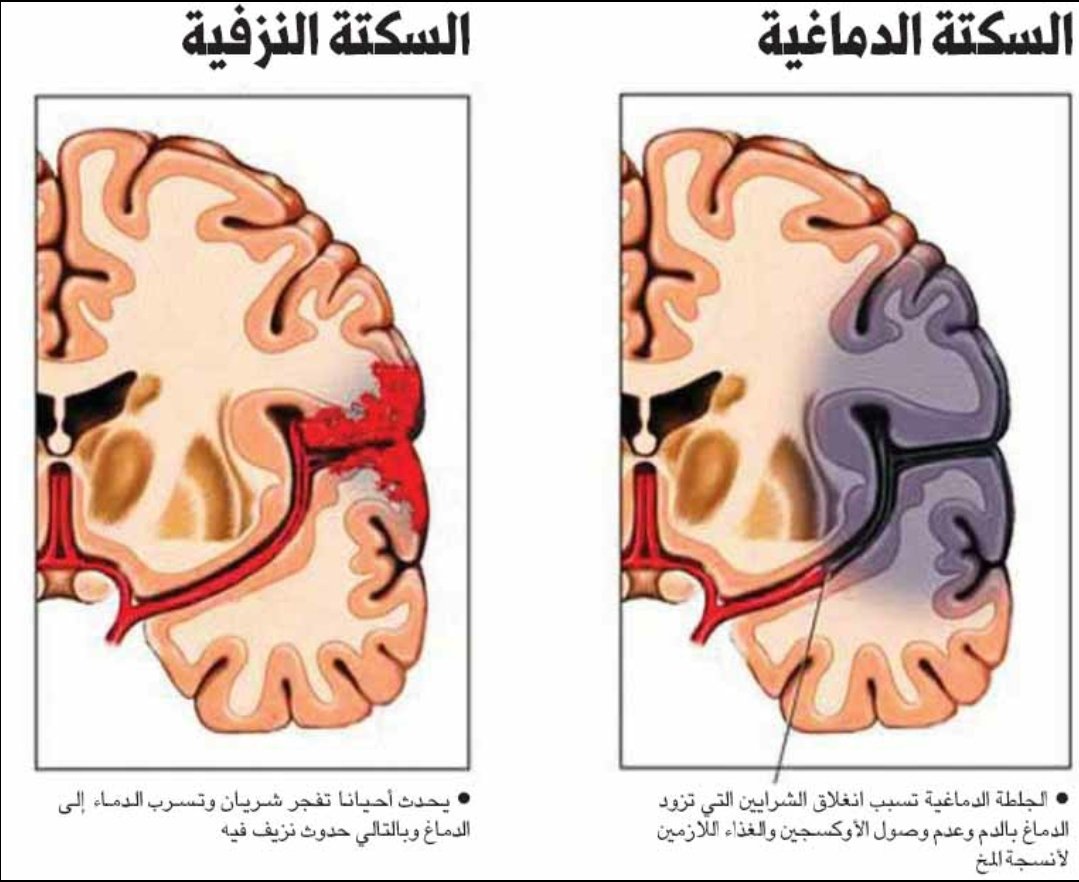

💥هي نقص ترويه الدم (الاوكسجين) لمنطقه بالمخ اوالحبل الشوكي اوشبكية العين

💥انواعها(اقفاريه ونزفيه)

🧠 انسداد في الشرايين (#السكته_الدماغيه_الاقفاريه)

🧠 انفجار الشرايين (#سكته_دماغيه_نزيفيه)

💥انواعها(اقفاريه ونزفيه)

🧠 انسداد في الشرايين (#السكته_الدماغيه_الاقفاريه)

🧠 انفجار الشرايين (#سكته_دماغيه_نزيفيه)

#السكته_الدماغيه_النزيفيه

بسبب إنفجار احد الشرايين او انسداد الاوردة

💥هي نقص في ترويه الدم للمخ اوالحبل الشوكي اوشبكيةالعين

💥بسبب (انسداد أو تضيق) في شرايين(القلب،الرقبه،الراس) الموصله للدم او الاورده المصرفه